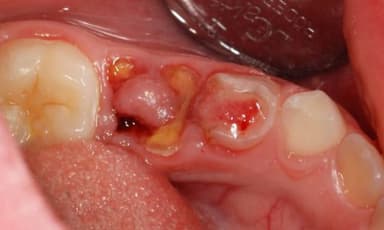

Như đã chia sẻ phía trên, sâu răng bị lồi thịt không phải là một thuật ngữ chính thức trong nha khoa, nó thường được sử dụng để mô tả tình trạng sâu răng nghiêm trọng, khi mà phần sâu của răng đã phá hủy nhiều mô răng và tiến triển vào các lớp trong, ảnh hưởng đến mô mềm xung quanh, như nướu và các mô lân cận khác. Trong một số trường hợp, tình trạng này có thể dẫn đến việc hình thành các ổ áp xe xung quanh răng, khi vi khuẩn từ răng sâu lan vào các mô, gây sưng, đau và có thể có mủ.

Sâu răng lồi thịt có thể dẫn đến việc hình thành các ổ áp xe xung quanh răng.